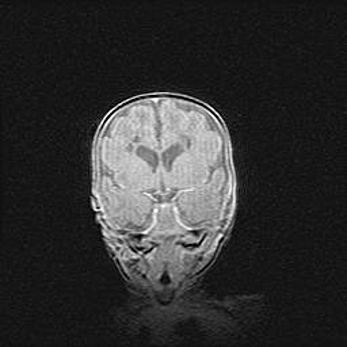

Множественные кисты обоих полушарий головного мозга, наибольшая из них в правой затылочной области. Ассиметричная атрофическая гидроцефалия.

Возраст: 7 месяцев

Вес: 5660 г

Пол: мужской

Окружность головы: 41,5 см

Срок гестации: 28-29 недель

Кисты головного мозга развиваются в результате многоочаговых некрозов вещества мозга и возникают вследствие перенесенной перинатальной инфекции, менингитов, энцефалитов, асфиксии, родовой травмы, расстройств мозгового кровообращения различного генеза. Образованию кист в веществе головного мозга плодов и новорожденных способствуют такие факторы, как высокое содержание в нем воды, недостаточная (или отсутствие) миелинизация и слабая астроглиальная реакция на повреждение.

Кисты могут сочетаться с гидроцефалией и другими поражениями головного мозга.